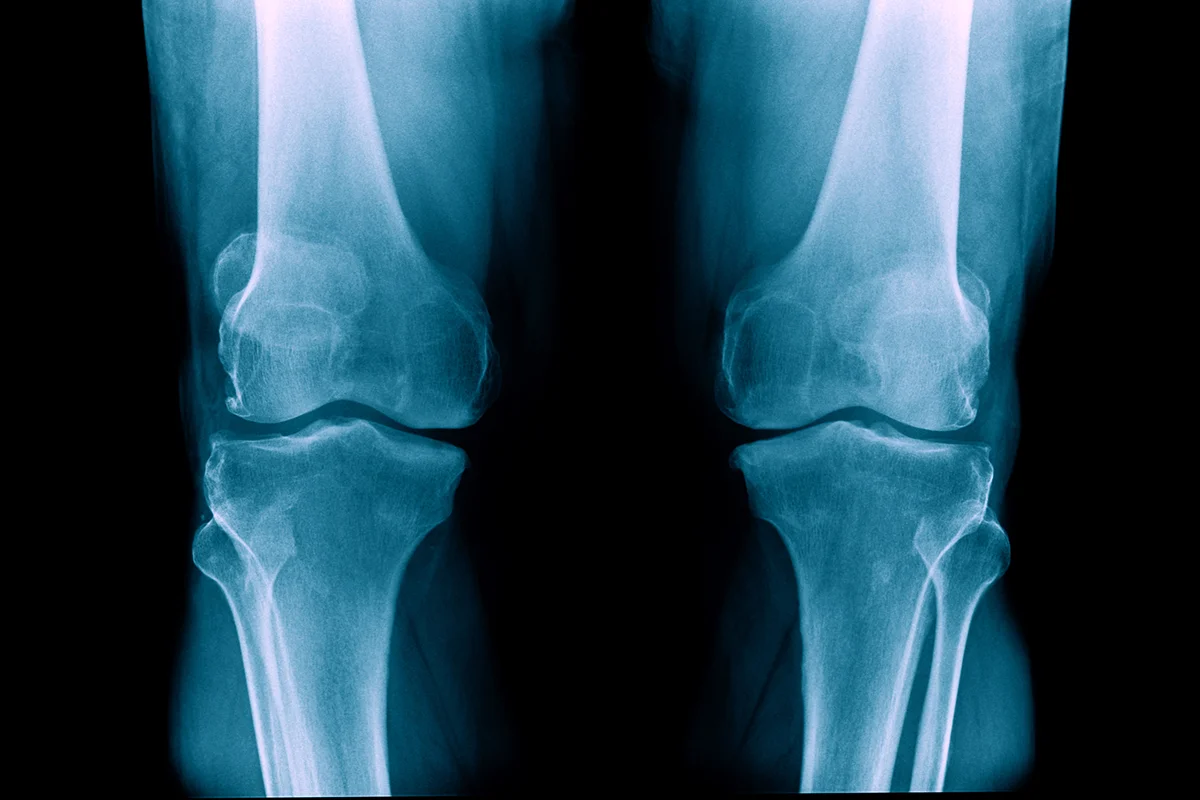

röntgenaufnahme der knie bei knieschmerzen

Was haben die Füße mit Knieschmerzen zu tun?

Wenn du Knieschmerzen hast, denkst du wahrscheinlich zuerst ans Knie selbst – vielleicht an eine Verletzung, eine Überlastung oder einfach „Verschleiß“. Doch unser Bewegungsapparat ist ein ausgeklügeltes System. Alles hängt zusammen: Sprunggelenk, Knie, Hüfte, Rücken – und ja, auch der Fuß.

Viele herkömmliche Schuhe haben einen Absatz, also eine sogenannte Sprengung zwischen Ferse und Zehen – meist zwischen 10 und 15 Millimeter. Dieser Höhenversatz bringt deinen gesamten Körper leicht aus dem Gleichgewicht. Deine Gelenke – vor allem Knie und Hüfte – müssen das ständig ausgleichen. Das Knie steht dann nicht mehr natürlich über dem Fuß, sondern wird seitlich oder schräg belastet. Das kann langfristig zu Beschwerden führen.